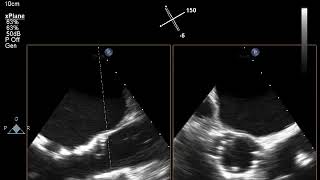

Video 1

Aortic valve pre-transcatheter aortic valve replacement.

Video 2

Aortic valve post-transcatheter aortic valve replacement.